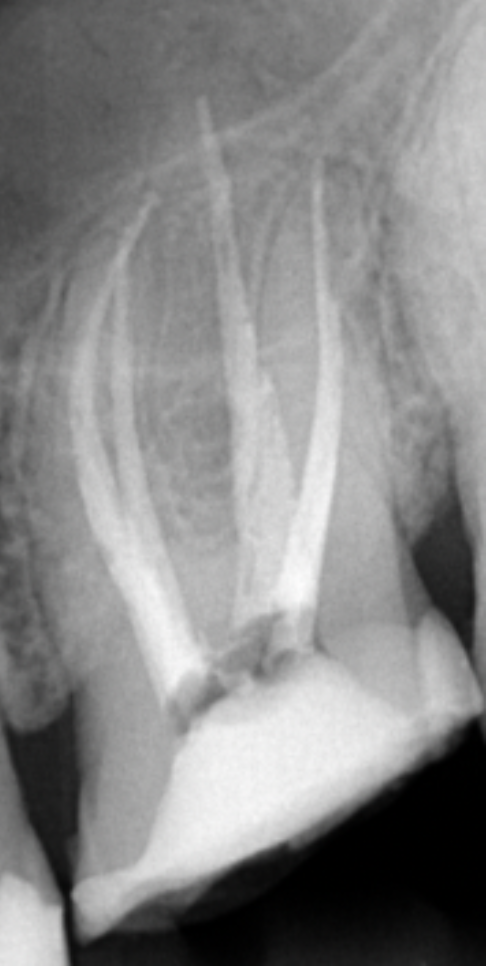

Przed leczeniem kanałowym wykonano zdjęcie rentgenowskie (ryc. 2). Ze względu na obecność żywej miazgi wykonano znieczulenie nasiękowe 1 ampułką Citocartin 100 (Molteni Dental). W osłonie koferdamu Blossom z zastosowaniem klamry 12A firmy Hygenic usunięto opatrunek. W powiększeniu mikroskopu Zumax wykonano dostęp endodontyczny wiertłem różyczkowym z węglika spiekanego o rozmiarze 014. Komora została poszerzona w kierunku mezjalno‑dystalnym. Odsłonięto ujścia czterech kanałów korzeniowych – MB1, MB2, DB1, P. Wykonano negocjację pilnikiem C‑file 10 (VDW) z pomiarem długości roboczej za pomocą endometru (VDW Reciproc Gold). Dokładna inspekcja dna komory w powiększeniu mikroskopu pozwoliła dostrzec dwa kolejne ujścia – MB3 i DB2. Występowanie kanału MB3 i DB2 jest znacznie rzadsze niż MB2 i DB1 i znajdują się one bliżej kanału podniebiennego. Negocjację kanałów MB3 i DB2 rozpoczęto od pilnika C‑file 10, zaginając narzędzie na kształt litery J (ryc. 3) – nie uzyskano pełnej długości, dlatego w kolejnym etapie użyto narzędzia 08, zaginając je na kształt litery A (ryc. 4); również nie uzyskano pełnej długości roboczej. Narzędzie C‑file 06 zagięte na kształt litery A osiągnęło otwór wierzchołkowy – potwierdzono długość roboczą i przystąpiono do wykonywania ruchów góra‑dół, bez nakręcania zegarka.

Ryc. 4. Zagięcie narzędzia na kształt litery A.